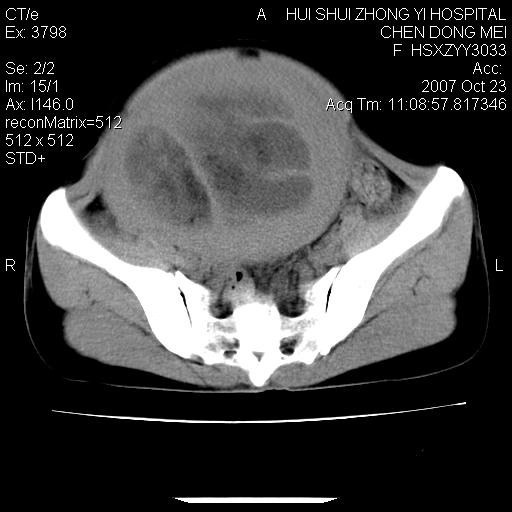

标题: CT10156:女.43岁,发现中下腹部包都块2年 [打印本页]

标题: CT10156:女.43岁,发现中下腹部包都块2年

发现中下腹部包都块2年。2年来月经不规律。

腹腔巨大软组织密度影,边缘光滑,包膜完整,内囊变坏死。腹膜后及盆腔内淋巴结肿大。结合病史考虑卵巢癌可能性大。

病灶内可见脂肪密度影,考虑畸胎瘤可能性大

病变巨大,呈囊实性改变,包膜较厚且完整,内见分膈,周围脏器明显受压移位,病变与左侧附件关系密切,考虑来源左侧附件的囊腺瘤,不除外癌变可能;畸胎瘤可能性较小。

病变巨大,呈囊实性改变,包膜较厚且完整,内见分膈,周围脏器明显受压移位,病变与左侧附件关系密切,考虑来源左侧附件的囊腺瘤,盆腔内见肿大淋巴结,不除外癌变可能。

病变巨大,呈囊实性改变,包膜较厚且完整,内见分膈,周围脏器明显受压移位,病变与左侧附件关系密切,考虑来源左侧附件的囊腺瘤,不除外癌变可能